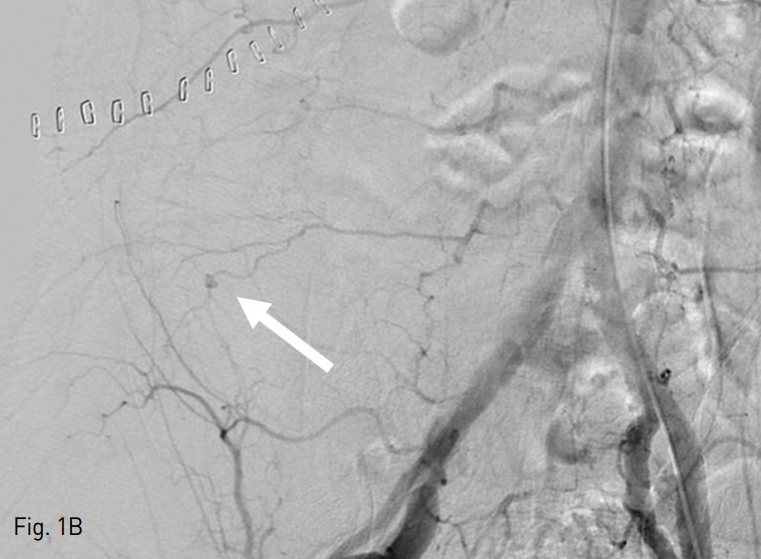

Fig. 1. A 75-year-old man with Jackson-Pratt catheter tract bleeding after radical excision of right kidney.

B. An aortogram showed the extravasation in the rightlower quadrant, which was well matched to the CT image findings.